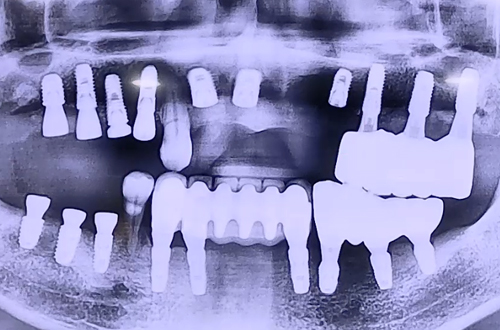

BEFORE

환자분은 이전 왼쪽에 임플란트를 진행하셨었고,

임플란트가 되지 않은 오른쪽 위아래 어금니와 위 앞니가 심하게 흔들거려서

거의 왼쪽으로만 식사를 하고 계시는 상태에서 내원해 주셨습니다.

때문에 오른쪽 위아래 어금니와 윗니 앞니를 임플란트를 통해서 단단히 하고

치아의 기능을 회복시켜드리는 방향으로 치료 계획을 세웠는데요.

불편한 치아들을 발치하고 임플란트를 단단히 심어드렸고,

임플란트는 굉장히 단단하게 잇몸뼈와 잘 결합되고 주변 뼈이식까지 잘 진행되었어요.

만약 심으려는 임플란트가 단단할 경우 당일에 바로 임시치아를 체결해 드리는데

환자분게서는 위 앞니 주변 잇몸뼈들이 약해서 즉시 임시치아 체결은 불가능했습니다.

따라서 위 앞니 임플란트를 잇몸 속으로 완전히 묻어두고 시간이 지나 스스로 굳게 하기로 하고

임시치아는 끼우고 빼는 타입으로 제작하여 드렸던 케이스입니다.